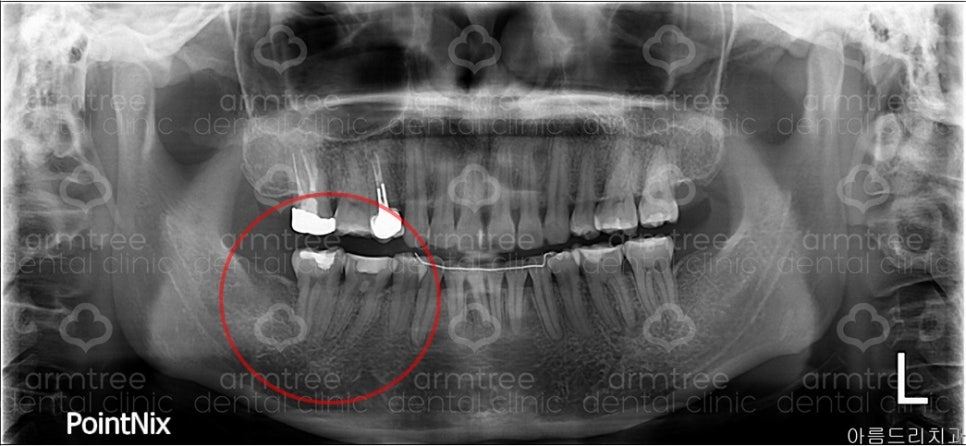

1번 사진] 환자 x-ray

환자분은 검사 결과 오른쪽 아래 6번과 7번 치아에 통증이 있었습니다. 그 치아로 인해 전체적으로 다 아픈 것처럼 느낀 것이었지요. 1번 사진 큰 엑스레이에 보시면 6번 7번 치아에 하얗게 예전에 치료한 흔적이 보입니다. 레진이라는 재료를 이용해서 충치 자리를 메꾼 것이지요. 그런데 아마 예전에 치료할 당시 충치가 크고 깊었을 것입니다. 충치가 깊으면 치료를 했어도 치아에게는 지속적인 자극이 될 수 있습니다.

이 환자분은 6번과 7번 모두 아파하셨기에 둘 다 신경치료를 할 수도 있었지만, 제 경험으로는 6번이 원인 치아이고, 7번은 연관통(6번으로 인해 같이 아픈 것으로 착각하는 것)이라고 판단되어 7번 치아는 건드리지 않고 6번 치아만 신경치료를 시작하였습니다.

만약 7번도 신경치료했다면 환자에게는 큰 손해였겠지요. 다만 문제는 6번 치아의 신경관이 막혀있다는 것입니다.

6번 치아는 보통 3개의 신경관이 있습니다.

신경치료를 시작해보니 3개의 관이 전부 막혀있네요.

여러 가지 장비를 동원하여 1개의 신경관을 잘 뚫었습니다만 2개는 정말 뚫리질 않네요. 통증이 많이 좋아진 상태이기 때문에 막힌 신경관을 무리해서 뚫을 필요는 없습니다.

상태를 지켜본 후에, 통증이 없어진다면 이 상태로 마무리할 계획입니다. 만약 통증이 줄어들지 않는다면, 치아재식을 치료를 할 예정입니다.